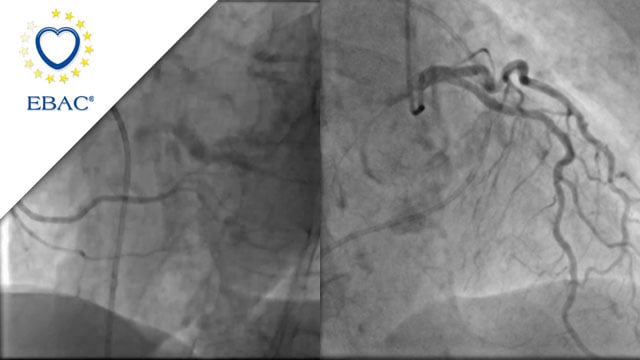

How should I treat a left main disease with multivessel diffuse CAD? Stenting only the necessary...

A 71-year-old male patient with a clinicial history of hypertension, dyslipidemia and active smoking was admitted for NSTEMI.

Coronary angiography showed a left main (LM) stenosis involving the bifurcation and proximal parts of the left anterior descending (LAD) and left circumflex (LCx) arteries. Right coronary artery (RCA) showed a severe...

Author